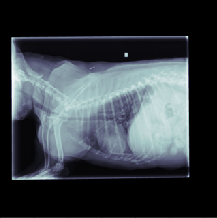

The data for this work consists of 390850 X-ray images, taken from 98660 veterinary sessions. These images were annotated by radiologists for over 41 diseases in a multi-label fashion, and are feedback from the usage of the RapidRead tool. Additionally, we have a dataset of 800 images with high-quality annotations, where the annotations were performed by 12 radiologists collaborating on each image. A sample of these X-ray images is shown in Figure 2.

This section presents visualizations of the Vision Transformer (ViT) attention maps. The ViT used is specific to lung diseases, and the attention maps are shown for patients with the positive label ’Pulmonary Mass’. The input to the ViT is a concatenated feature map, and the X-ray images have been mapped and displayed with the same concatenation and transformations applied to the augmented feature maps.

The attention maps show that the ViT focuses on the thorax region where the lungs are located, as expected. The results also demonstrate that the ViT remains focused on the thorax area even with different contexts in the X-ray images. This highlights the robustness of ViTs.